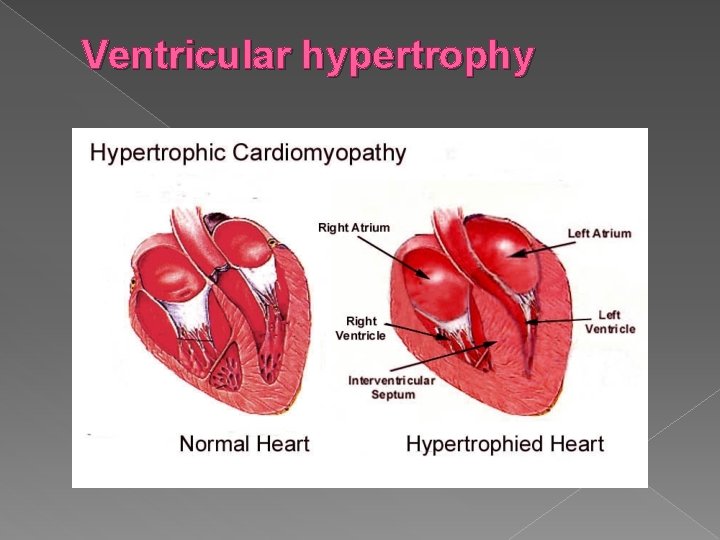

Ventricular hypertrophy › In utero - hypertrophy is most commonly associated with cardiac outlet obstruction but may be associated with maternal diabetes.